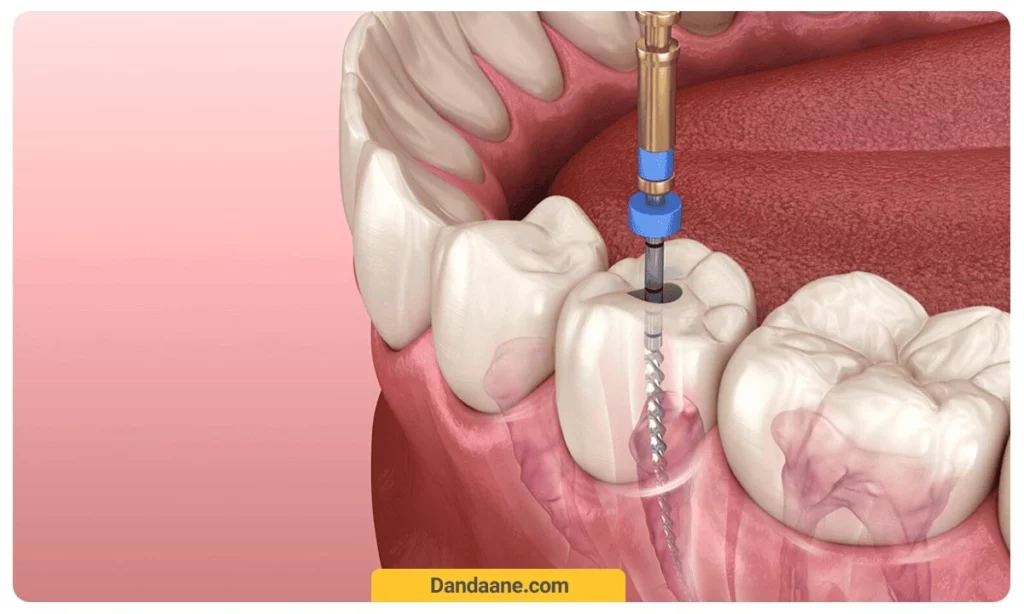

3. عصب کشی در صورت آسیب به پالپ دندان

در مواردی که ترک به عصب دندان رسیده باشد، عصبکشی ضروری است. در این روش، عصب آسیب دیده خارج شده و دندان با مواد مخصوص پر می شود تا از شکستگی بیشتر جلوگیری شود.